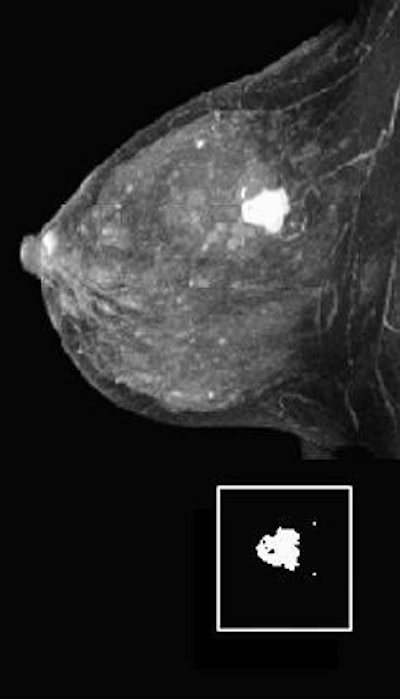

|  |

| Same patient. Above, parametric washout image shows tumor is isolated from rest of breast. Surrounding pixels (arrows) correspond to washout value smaller than 23 (i.e., cutoff value chosen by observer) and were there excluded from volume processing. Below, applying cutoff and processing volume of remaining pixels resulted in this parametric washout image. El Khoury C, Servois V, Thibault F, Tardivon A, Ollivier L, Meunier M, Allonier C, Neuenschwander S, "MR Quantification of the Washout Changes in Breast Tumors Under Preoperative Chemotherapy: Feasibility and Preliminary Results" (AJR 2005; 184:1499-1504).  |